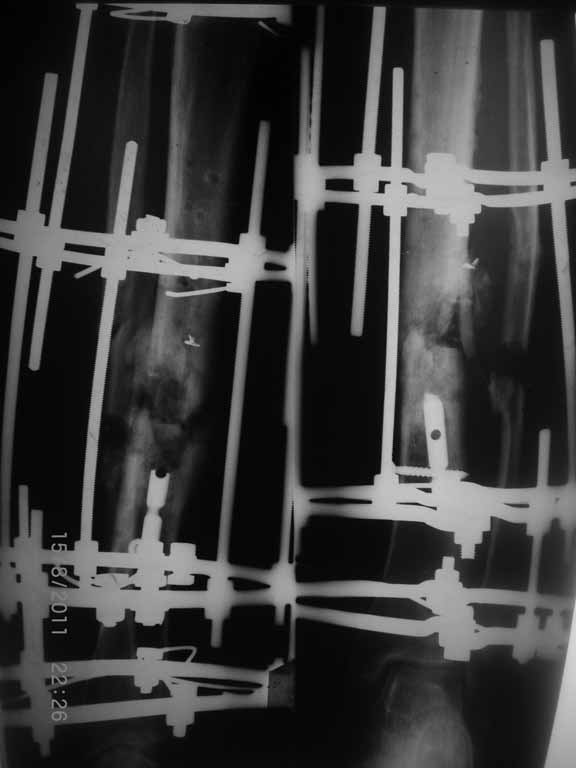

Это гипотрофический ложный сустав. Проблем видится несколько:

1. нарушение трофики в месте перелома.

2. после фиксации в аппарате Илизарова на рентгеногнрамме имеются признаки спицевого остеомиелила. В настоящи момент хотя свищей нет с мая 2011 нет опасно ли фиксировать голень стержнем?

На основании каких признаков Вы решили, что кость мертвая! Имеется гиперпластический ложный сустав, как результат недостаточно стабильной фиксации ан предыдущих этапах лечения. В данном случае необходимо решение следующих вопросов:

1 наличие инфекция в зоне ложного сустава

2. коррекция оси

3. окончательная стабильная фиксация

4. исключение предыдущих ошибок

5. оценка своих возможностей.